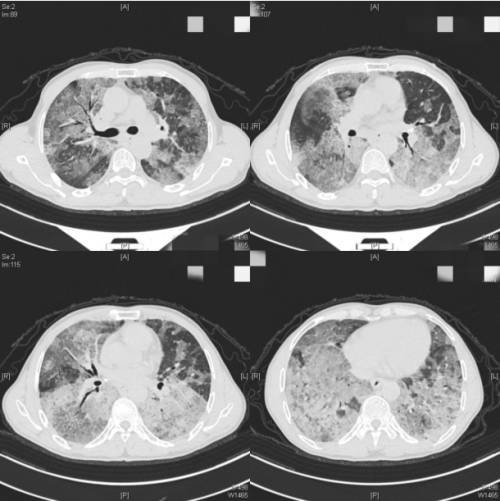

(南华大学附属长沙中心医院)呼吸与危重症医学科求诊。入院时,医生发现常先生血氧饱和度仅为60%(正常人是95%以上),胸部CT显示双肺弥漫性病变,血气分析提示严重I型呼吸衰竭,查体双肺可闻啰音(弥漫性肺间质纤维化患者吸气后期出现的声音),杵状指(部分晚期患者可出现此症状)。科室迅速完善支气管镜活检,诊断其为肺泡蛋白沉积症,俗称“牛奶肺”。

患者入院时肺部广泛弥漫性病变

“肺泡蛋白沉积症是以肺泡表面活性物质灶肺泡巨噬细胞和肺泡腔内异常沉积导致的以呼吸困难为主的弥漫性肺疾病,是罕见的呼吸系统疾病。”据呼吸与危重症医学科主任、主任医师杨红忠介绍,肺泡蛋白沉积症可分为原发性、继发性和先天性,原发性是目前发病率最高的类型,但也需警惕继发于血液系统疾病、恶性肿瘤等所致的继发性肺泡蛋白沉积症,主要症状为胸闷、呼吸困难、咳嗽、咳痰、咯血等,临床症状及体征轻,影像学表现重,肺部CT表现为“铺路石”“地图样”改变。